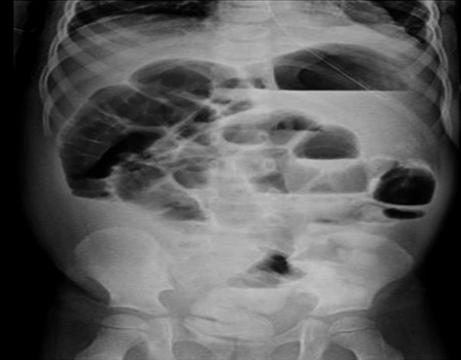

El paciente presentó evolución posquirúrgica inmediata adecuada, con Doppler esplénico a las 24 horas que evidenció bazo bajo la modalidad doppler, pulsado y codificado por color curvas espectrales fasicas normales y adecuadas en el hilio esplénico, confirmando adecuada perfusión esplénica. Se realizó manejo de dolor posquirúrgico con catéter peridural con infusión de bupivacaína al 0.1%, que fue retirado al tercer día posquirúrgico. Presentó íleo posquirúrgico en el cuarto día (Ver Figura 4) se dio manejo médico (reposo gástrico, sonda nasogástrica, deambulación e hidratación endovenosa) con evolución clínica satisfactoria a las 48 horas, por lo que se indicó egreso.

Figura 4 Radiografía de abdomen decúbito supino con hallazgos sugestivos de íleo posquirúrgico.